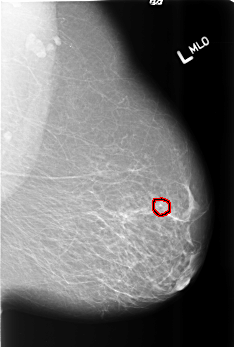

B_3473_1.LEFT_MLO

LEFT_MLO LINES 5544 PIXELS_PER_LINE 3736 BITS_PER_PIXEL 12 RESOLUTION 50 OVERLAY

FILE: B_3473_1.LEFT_MLO.OVERLAY

TOTAL_ABNORMALITIES 1

ABNORMALITY 1

LESION_TYPE CALCIFICATION TYPE PLEOMORPHIC DISTRIBUTION CLUSTERED

ASSESSMENT 4

SUBTLETY 4

PATHOLOGY BENIGN

TOTAL_OUTLINES 1

BOUNDARY